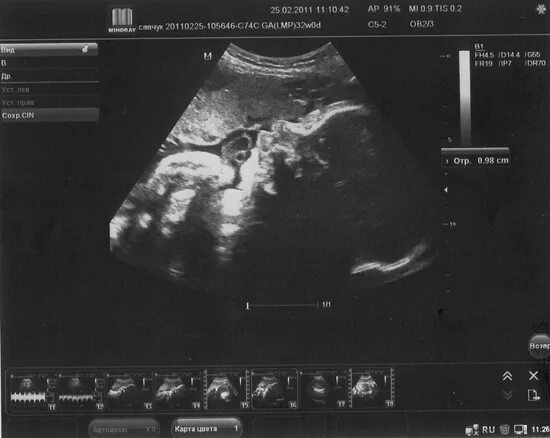

Норма плода на 33 неделе